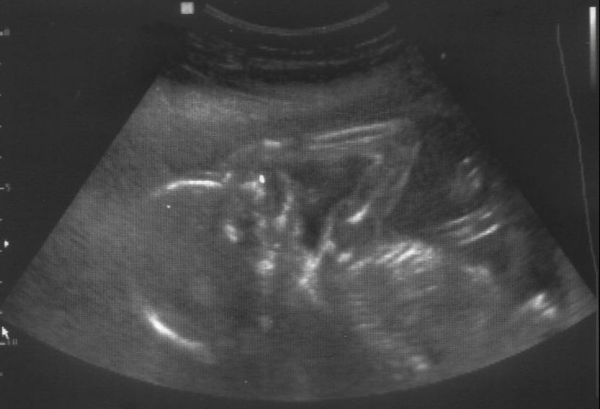

Végre megvolt az UH, szerencsére minden rendben a Picurkával a doki szerint is.

Az UH minősége nem volt valami jó, túl sokat nem láttunk, na meg persze se kép, se semmi.

De legalább láthattuk őt végre egy rövid ideig!

Magzat medencevégű fekvésben

BPD: 44 mm, HC: 160 mm, AC: 135 mm, FL: 30 mm.

Négyüregű szív, ritmusos szívműködés, épnek imponáló koponya és gerinc.

Ép hasi és mellkasi szervek, ép rekesz.

Ép, hiánytalan, hosszú csöves csontok.

Jó hólyagtelődés ábrázolódik, gyomortelődés sejthető.

Magzatvíz mennyisége átlagos, placenta a fundusban tapad

Magzati malformatiora utaló UH jel nem látható.